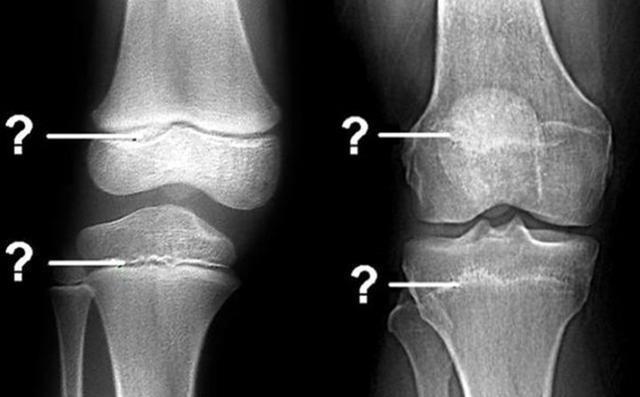

骨骺线闭合是孩子“身高”封锁的信号,要想蹿出高个子,家长要有数

在一些家长看来,判断孩子是否还有发育潜力的关键在于年龄,事实上,这种判断并不准确,

相反,骨骺线才是决定孩子能否长高的关键参数。

▼什么是骨骺线?

骨骺线其实指的是骨骼之间的软骨层,这些软骨层之间会存在一定的空腔,这些空腔的存在就为接下来的身高发育提供了无限的可能。

体内的骨细胞会在空腔中不断增殖再生,同时骨质化,从而让宝宝不断长高。

文章插图

相反,如果孩子的骨骺线出现了闭合,那么说明软骨层的空腔已经闭合,

【 孩子|要想孩子冲破“身高封锁线”,建议家长抓住三个信号,能多长5cm】骨细胞没有“地方”转变为骨质帮助长高

,孩子的身高发育也就告一段落。